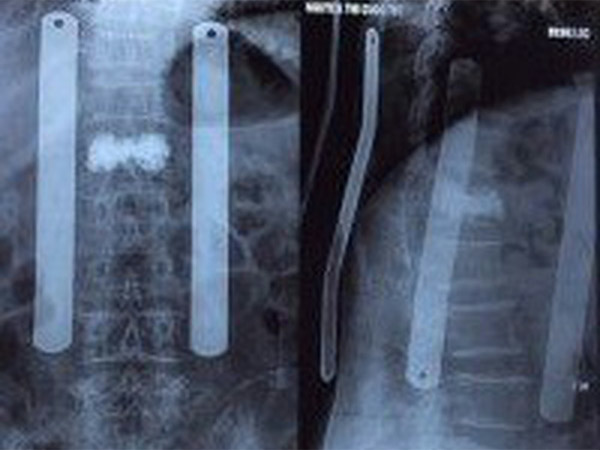

Chẩn đoán hình ảnh là quyết định để đánh giá VF. Xquang cột sống ngực thắt lưng thẳng nghiêng thường quy thường được sử dụng nhất để đánh giá ban đầu VF. Tuy nhiên chỉ xquang thường không đánh giá được hết mức độ và tổn thương. MRI thường được chỉ định, nó có thể xác định được chính xác xẹp đốt sống cấp và bán cấp tính, đánh giá hình thái của VF, và phát hiện được một số bệnh kèm theo có thể là chống chỉ định của VP. Thêm vào đó, những đốt sống VF kín đáo khó phát hiện trên Xquang có thể được phát hiện dưới MRI giúp tránh bỏ sót tổn thương. Hình ảnh đốt tổn thương trên MRI do sự phù tủy xương cấp tính, bán cấp tính hoăc VF không được chữa lành, có hình ảnh giảm tín hiệu trên thì T1, tăng tín hiệu trên thì T2 và STIR.

Với bệnh nhân không thể chụp MRI, xạ hình xương có thể được chỉ định để phát hiện đốt sống xẹp cấp tính. CT cũng có thể được chỉ định để xác định VF, hơn thế nữa CT còn dùng để đánh giá tường sau của đốt sống và đánh giá các mảnh xương vỡ.